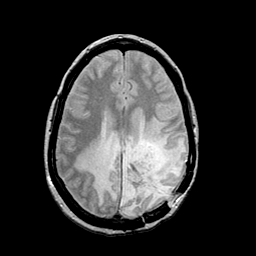

MR Study #2 -- Slice #35